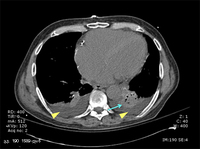

პაციენტის კომპიუტერული ტომოგრაფია, რომელსაც აქვს დიდი, მკვრივი ინფილტრაცია მარცხენა ქვედა წილში.

თანხმობა მიღებულია ლუისვილის უნივერსიტეტში, ლუისვილი, კენტუკი